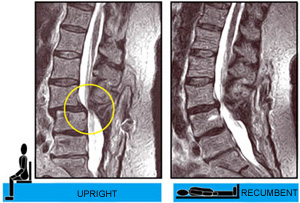

Knowing the full extent of pathology and the differences in anatomy between the upright and recumbent positions can be critical. Lie-down-only

MRIs cannot detect pathology that is visible only when the patient is scanned in an upright position. A lie-down scan may also underestimate

the maximum degree of pathology and miss its dynamic nature. Only the UPRIGHT® MRI (also known as the Stand-Up® MRI) gives the

complete picture of your patients’ problems.